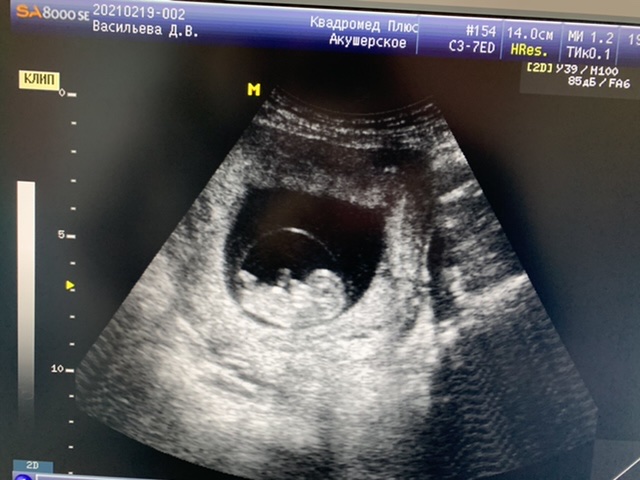

фото должно быть четко в профиль, тут под углом развернут малыш, непонятно

Рано ещё, хотя бы недель 12 было бы, что бы половой бугорок видно было. И на фото ножка все закрывает

По этому фото не понятно, слишком далеко

Ничего тут не видно))

Я правильно понимаю, что это вид с попы, а вверху два яичка и пенис?) Или меня уже глючит в ночи)

Это вид сбоку)как он объяснил,под ножками писька)

По этому фото непонятно,тут ножки видны,должен быть немного другой снимок.По головешке больше на пацана похоже,но это все 50 на 50))

А как вы поняли что парень?На фото никаких половых признаков :) Мне внешне девочку напоминает,по профилю если смотреть))

Узист сказал-видно письку)

Ну, это он так выразился, видимо😊 На таком сроке письку не видно толком, потому что только формируется всё. Там половой бугорок, который что у мальчиков, что у девочек - очень похожи. Разница только в наклоне его. С правильного ракурса бугорок можно рассмотреть и предположить, кто будет.

Пол в 14 недель Узи девочка